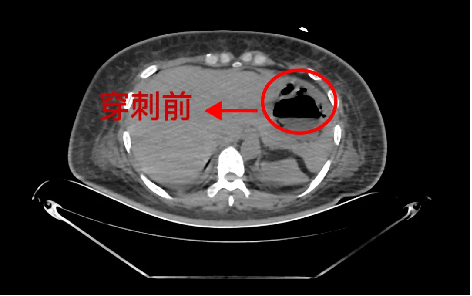

重症医学科主任杨徳军仔细查看患者情况后,结合检查结果,考虑患者是肝脓肿诱发糖尿病酮症酸中毒。急请普外科会诊,普外科学科带头人龚昭教授和副主任医师余勇会诊后,一致诊断患者为急性肝脓肿,立即为患者行CT引导下穿刺置管术,抽取咖啡色样液体送检,并留置引流管引流。引流液培养结果为“高毒力肺炎克雷伯杆菌感染”。经过3天针对性的抗感染治疗及脓液引流,患者生命体征平稳,感染指标下降,成功转入普通科室进一步康复治疗。